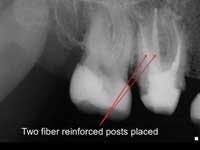

Less than one-half of the coronal tooth structure remaining (Figs. 1-6)

It is my opinion, regardless of the other factors present, that it is still advisable to place a post or posts in such teeth. Endodontically treated teeth with less than one-half of the coronal tooth structure remaining have a reduced chance of long-term service, and patients should be so advised as the treatment plan is developed.

No tooth structure remaining coronal to the gingival tissue

There are clinical situations in which these teeth should be retained, including if the practitioner plans to extrude the tooth orthodontically. However, when considering the clinical success of dental root-form implants compared to questionable teeth, it is often better to extract the teeth and place implants. In the debatable event that a decision is made to restore such teeth, a post in single-rooted teeth or more than one post in multirooted teeth should be placed. Even with adequately placed posts present, the long-term success of such teeth is very questionable.